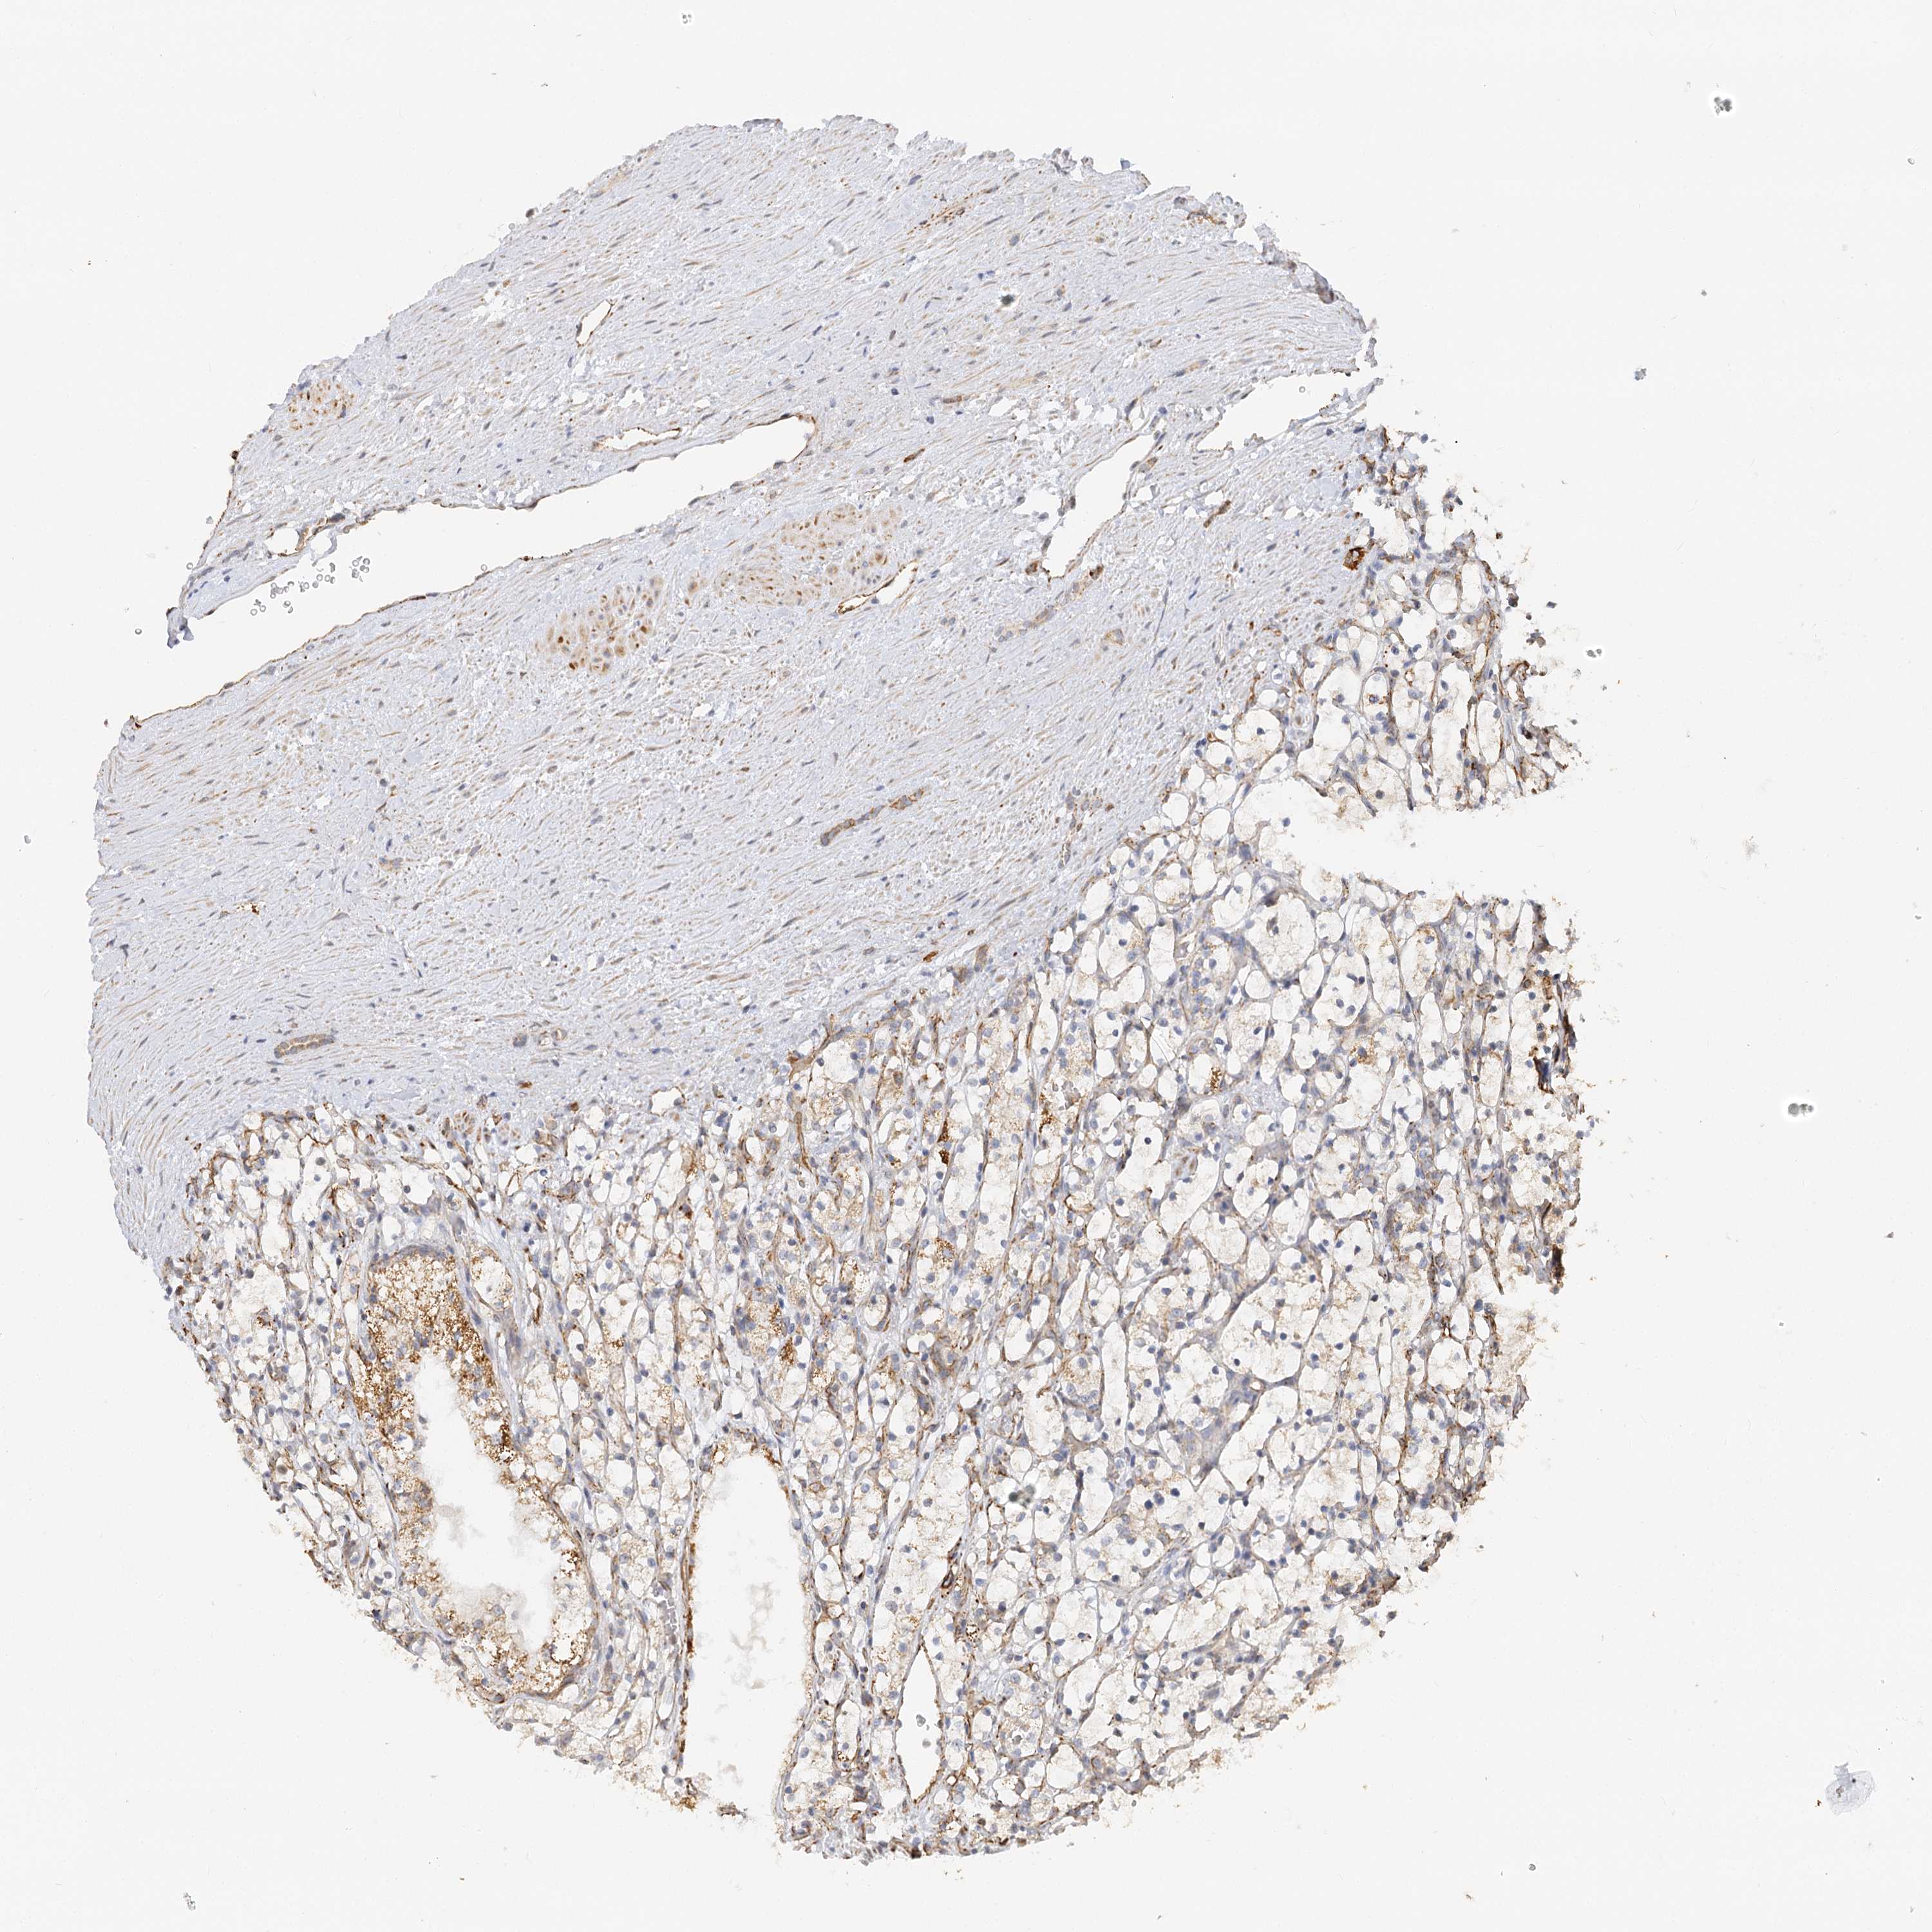

KIDNEY RENAL CLEAR CELL CARCINOMA (VALIDATION) - Interactive survival scatter ploti

The Survival Scatter plot shows the clinical status (i.e. dead or alive) for all individuals in the patient cohort, based on the same data that underlies the corresponding Kaplan-Meier plots. Patients that are alive at last time for follow-up are shown in blue and patients who have died during the study are shown in red.

The x-axis shows the expression levels (FPKM) of the investigated gene in the tumor tissue at the time of diagnosis. The y-axis shows the follow-up time after diagnosis (years). Both axes are complimented with kernel density curves demonstrating the data density over the axes. The top density plot shows the expression levels (FPKM) distribution among dead (red) and alive patients (blue). The right density plot shows the data density of the survived years of dead patients with high and low expression levels respectively, stratified using the cutoff indicated by the vertical dashed line through the Survival Scatter plot. This cutoff is automatically defined based on the FPKM cutoff that minimizes the p-score. The cutoff can be changed by dragging the vertical line or by entering a cutoff value in the square labeled "Current cut-off".

Under the Survival Scatter plot the p-score landscape (black curve; left axis) is shown together with dead median separation (red curve; right axis). Dead median separation is the difference in median mRNA expression between patients who have died with high and low expression, respectively. It is calculated as follows: median FPKM expression of dead patients with high expression - median FPKM expression of dead patients with low expression. This is intended to aid the user in visually exploring custom cutoffs and the associated p-scores and dead median separation.

Individual patient data is displayed and can be filtered by clicking on one or more of the category buttons on the top of the page. Categories describing expression level and patient information include: high, low, alive, dead, female, male and tumor stages. The scale of the x-axis can be toggled between linear and log-scale by clicking on the "x log" button. Mouse-over function shows TCGA ID, patient information and mRNA expression (FPKM) for each patient.

& Survival analysisi

Kaplan-Meier plots summarize results from analysis of correlation between mRNA expression level and patient survival. Patients were divided based on level of expression into one of the two groups "low" (under cut off) or "high" (over cut off). X-axis shows time for survival (years) and y-axis shows the probability of survival, where 1.0 corresponds to 100 percent.

NELL2 is not prognostic in Kidney Renal Clear Cell Carcinoma (validation)

: 2.69

Average pTPM 2.0

Number of samples 100